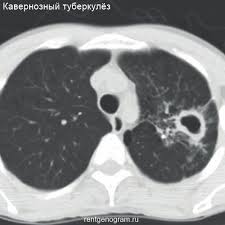

Infiltratiw inçekesel